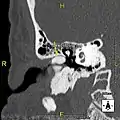

Surfer's ear is the common name for an exostosis or abnormal bone growth within the ear canal. They are otherwise benign hyperplasias (growths) of the tympanic bone thought to be caused by frequent cold-water exposure.[1] Cases are often asymptomatic.[1] Surfer's ear is not the same as swimmer's ear, although infection can result as a side effect.

Irritation from cold wind and water exposure causes the bone surrounding the ear canal to develop lumps of new bony growth which constrict the ear canal. Where the ear canal is actually blocked by this condition, water and wax can become trapped and give rise to infection. The condition is so named due to its high prevalence among cold water surfers, although it can occur in any water temperature due to the evaporative cooling caused by wind and the presence of water in the ear canal.

The normal ear canal is approximately 7 mm in diameter and has a volume of approximately 0.8 ml (approximately one-sixth of a teaspoon).[5] As the condition progresses, the diameter narrows and can even close completely if untreated, although people generally seek help once the passage has constricted to 0.5–2 mm due to the noticeable hearing impairment. While not necessarily harmful in and of itself, constriction of the ear canal from these growths can trap debris, leading to painful and difficult to treat infections.